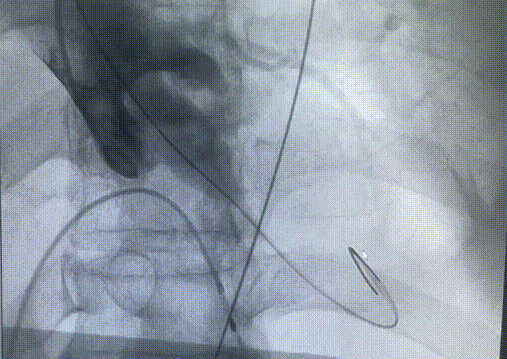

1. 患者钙化非常严重,Type 0型二叶瓣,钙化积分高达2100+,钙化主要分布瓣叶、瓣叶交界,升主动脉严重扩张,必要时使用Snare辅助过弓和跨瓣;

2. 患者主动脉弓角度在过弓时会遇到困难,并且降主动脉明显瘤样扩张,容易产生夹层;

3. 患者入路条件不好,双侧股动脉明显狭窄,术中会采用外周预扩球囊4.0mm、5.0mm及6.0mm逐步预扩张右侧股动脉和右髂动脉,造影验证预扩后情况,根据预扩张后情况决定是否采用右侧股动脉为主入路血管;

4. 患者入路血管左侧分叉高,无迂曲。

图片

20球囊预扩

输送系统定位